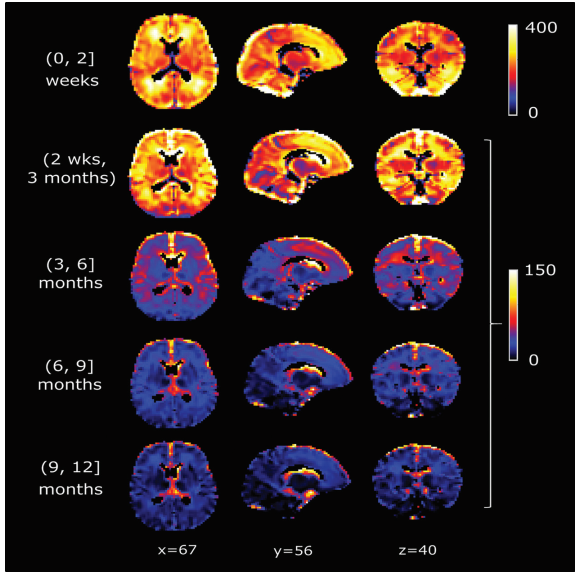

体素水平分析ADC下降率

体素水平ADC成熟年龄 。 A , 基于体素分析每个体素的ADC成熟年龄(以年为单位) 。 色标以年为单位显示 , 其中出生以深蓝色显示 , 3岁以红色显示 。 所有ADC的成熟都发生在3岁内 。 B , 每个体素在成熟时显示(以年为单位) , 使用与A相同的色标 。 两侧半球的成熟年龄显示出半球不对称性 。